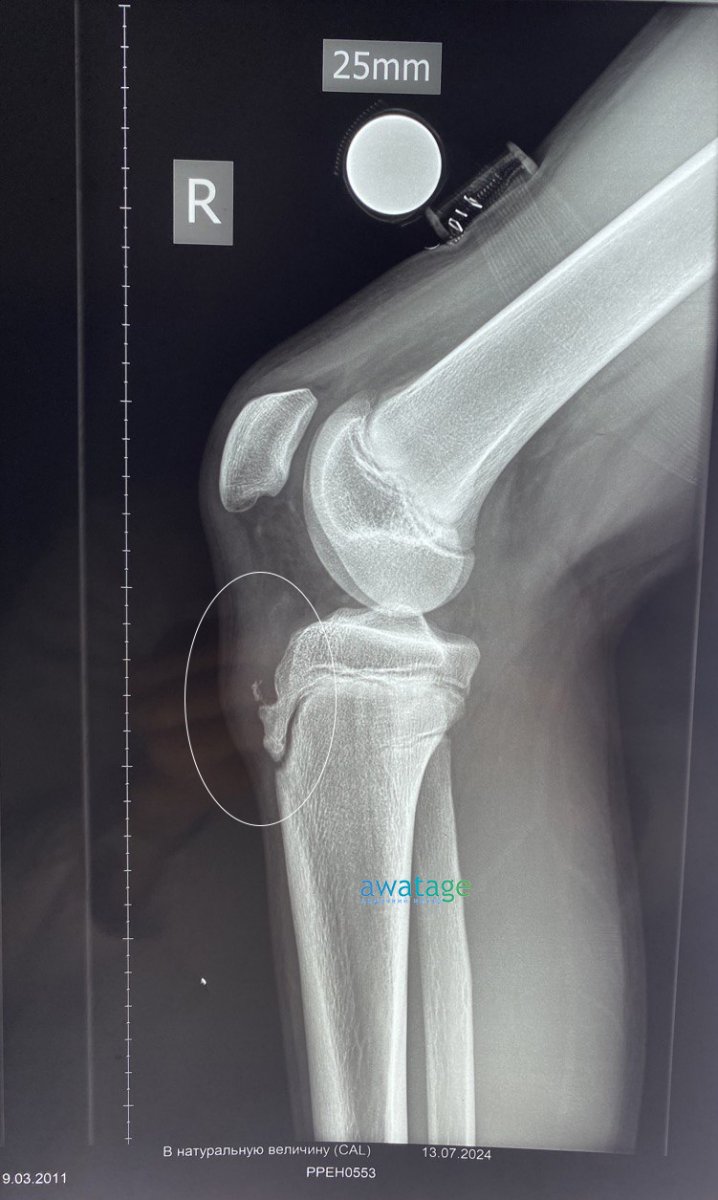

Когда ребенок-спортсмен жалуется на постоянную боль под коленом, и при этом он активно растет, то это может быть болезнь Шляттера. Обычно ее страдают подростки, особенно мальчики 10-16 лет, которые совмещают интенсивные тренировки, прыжки, бег или футбол с быстрым ростом костей. В результате месте воспаления появляется боль, припухлость и дискомфорт.

При быстром росте костей подростка точка крепления сухожилия мышцы бедра к большеберцовой кости оказывается под повышенной нагрузкой. Если в этот период ребенок активно занимается спортом?(баскетболом, футболом, гимнастикой, скачками), то?эта нагрузка становится хронической.

Сенсорная чувствительность может быть еще нормальной, но участок крепления сухожилия уже «раскаляется» от повторяющихся нагрузок, появляется боль при приседании, прыжках, спуске, подъеме по лестнице. Со временем без лечения возможны осложнения: хроническая боль, псевдоартроз, ранний артрит колена.